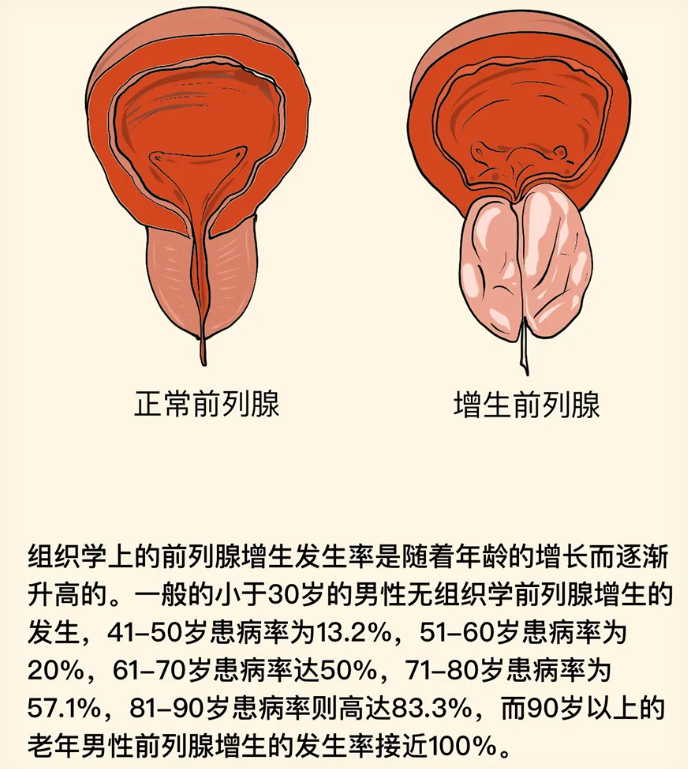

前列腺是男性特有的腺体,随着年龄增长,尤其在中老年阶段,前列腺组织会逐渐增生肥大。当前列腺体积增大时,会压迫穿行其中的尿道,从而引起一系列排尿症状。患者常感到排尿费力、尿流变细、射程变短,有时排尿后仍有滴沥,出现尿频、尿急,尤其是夜尿次数增多。如果梗阻加重,膀胱内残余尿增多,可能引起反复尿路感染,甚至影响肾脏功能。